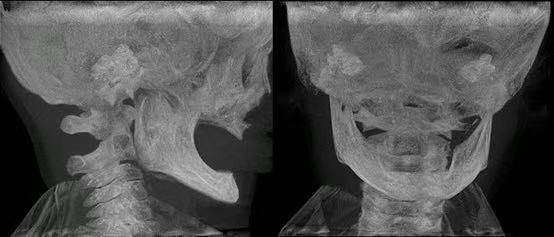

图片

CBCT显示其颌骨发育严重不足。

CBCT显示,乳牙胚和恒牙胚缺如,其上下颌骨发育短小,牙槽骨厚度、高度严重不足,最薄处仅1~2毫米,“如纸一般菲薄”。

与临床常见因牙齿早失导致骨吸收的无牙颌老人不同,HED患儿的颌骨从未经历正常发育过程,骨量基础更为薄弱。这一结构缺陷,不仅使全口义齿固位极为困难,更意味着未来成年后可能不具备接受种植牙手术的解剖条件